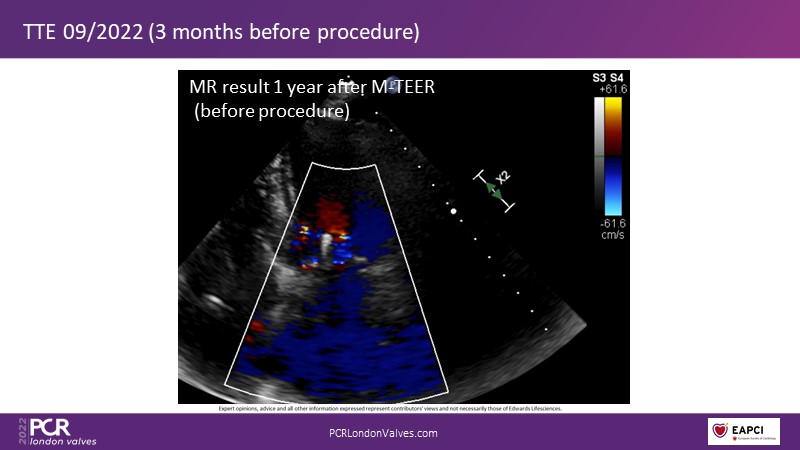

This innovative session takes you through the patient selection and anatomical characteristics when selecting amongst the different transcatheter options to treat tricuspid regurgitation, followed by a recorded demonstration using the PASCAL Precision repair system.